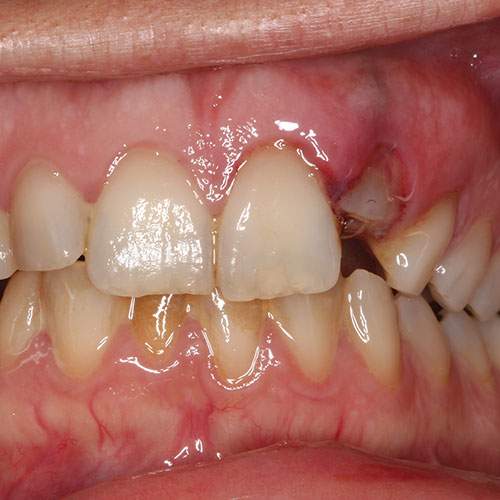

Clinical image: Labial view showing intrusion of UL2 with resultant ‘short clinical crown.

The incisal edge of the intruded tooth is more apical compared to adjacent teeth (giving the appearance of a fractured tooth with a resultant ‘short clinical crown’)

When the tooth is driven into the socket there may be disruption of the gingival margins